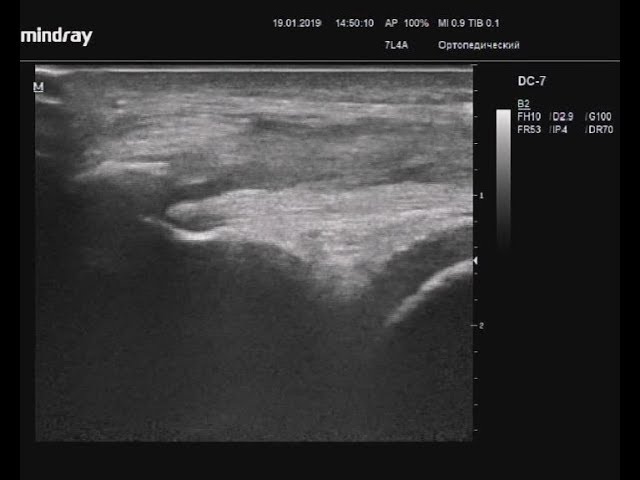

Такую травму можно диагностировать способом исключения, однако диагностирование не представляет трудностей, учитывая анамнестические данные (наличие прямой травмы) и клинические проявления. В некоторых случаях проводится рентгенографическое исследование для целей исключения сопутствующего перелома. Ультразвуковое исследование размеров кровоизлияния и мышечного дефекта позволяет различить остро сформировавшуюся гематому от диффузной отечности. Целесообразность МРТ с целью диагностирования сомнительна.